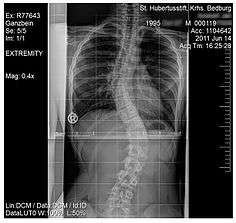

Scoliosis

Scoliosis, is a medical condition where a person's spine has several irregular curves that are located between the neck and the pelvis.[17] Symptoms of scoliosis in mild cases usually exhibit abnormal posture, back pain, tingling or numbness in the legs and in worse cases can exhibit breathing problems, fatigue, permanent deformities and in rare cases heart problems.[17]

Although the cause of scoliosis can sometimes remain unknown (idiopathic scoliosis) there is treatment available that targets at strengthening the back muscles, for milder cases usually do not require medical attention, more severe cases require either muscle strengthening exercises aimed at the back muscles and even special back braces or surgery can be recommended if the case is extreme.[17] Studies have shown that treatment with a special back brace among children ranging from 10–16 years can be successful and using this method of muscle training scoliosis can be cured with non-surgical treatment.[18]